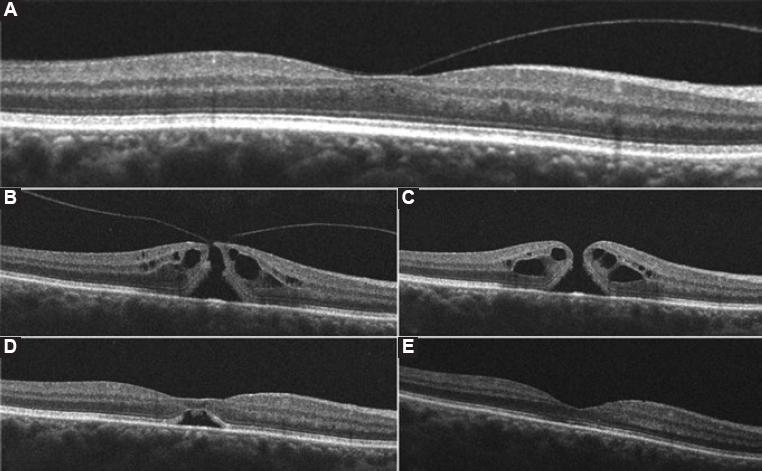

A 61-year-old woman with a previous history of hypothyroidism, cataract surgery on both eyes (OU) and broad vitreomacular traction (VMT) on the right eye (OD) (Fig. 1A), presented to the retina and vitreous clinic with a 10-day history of sudden-onset metamorphopsia and blurred vision OD. Best-corrected visual acuity (BCVA) was 20/125 OD and 20/20 on the left eye (OS). Anterior segment biomicroscopy revealed no alterations OU. Posterior segment examination by means of indirect ophthalmoscopy of OD showed around xanthophyllic circle with evidence of a small retinal defect in the center of the macula and a partial perifoveal posterior vitreous detachment (PVD) consistent with a Stage 2 IMH according to Gass' classification. Diagnosis confirmation with macular optical coherence tomography (OCT) demonstrated a primary small macular hole with VMT in agreement with the International Vitreomacular Traction Study classification system for macular hole11 (Fig. 1B). The rest of the posterior segment examination was unremarkable OU.

Figure 1 Horizontal high-definition optical coherence tomography images of the right macula and their correspondent best-corrected visual acuity (BCVA) at the time. A: Imaging before the onset of visual symptoms shows a split of the vitreous cortex with broad vitreomacular traction (VMT) and a resultant partial loss of foveal depression with intraretinal fluid (BCVA 20/20). B: Imaging after the onset of visual symptoms reveal perifoveal vitreous detachment, focal VMT along with a full-thickness hourglass shape defect of the neurosensory retina, surrounded by a cuff of intraretinal cysts; hole aperture size was 226µm and maximal foveal thickness was 433µm (BCVA 20/125). C: One week after gas injection a complete posterior vitreous detachment, rounding off the edges of the retinal defect and a slight increase in the cuff-like thickened zone of intraretinal cysts can be seen. Maximal foveal thickness was 450 µm (BCVA 20/100), D: 2 weeks after perfluoropropane injection an anatomic closure of the retinal defect with the partial morphological recovery of the foveal depression and a remaining subfoveolar neurosensory retinal detachment are demonstrated (BCVA 20/100), E: 4 weeks postoperatively, a full morphologic and functional recovery is shown with full anatomic integrity of inner and outer retinal layers (BCVA 20/20).

One week after the procedure, a macular OCT evidenced PVD and resolution of VMT with a subsequent increase in the maximal foveal thickness, intraretinal cysts and a decrease of the hole aperture size (Fig. 1C). By week 2 postoperatively, OCT evidenced anatomic closure, with a remaining subfoveolar neurosensory RD (Fig. 1D); and a BCVA of 20/100. Regular follow-up demonstrated progressive morphologic improvement with full neurosensory reattachment, restoration of normal foveal contour and preservation of cytoarchitecture of the inner and outer retinal layers with a BCVA of 20/20 OU 4 weeks postoperatively (Fig. 1E). After a 6-month follow-up, morphologic and functional stability were maintained. No adverse events due to the intravitreal injection of C3F8 were presented.

Intravitreal injection of 0.2 ml of C3F8 proved to be effective in producing PVD, the release of VMT and anatomic closure of Stage 2 IMH with long-term stability. Gass hypothesized that IMH's begin with tangential traction of the perifoveal vitreous cortex that results in foveal dehiscence and progress from foveolar detachment to full-thickness IMH2,3. The serial high-definition OCT images obtained in our patient support the current theory that the course of the condition begins with perifoveal PVD and is continued by anteroposterior and dynamic VMT12,13. The prevalence of IMH's has been estimated in 0.1-0.8% of adults aged >40 years with an age-adjusted incidence of 7.8/100,000 of the general population per year13. Two-thirds of patients are females and unilateral involvement is seen in about 80% of the cases14.

After PVD and VMT release, we observed in our patient a more even distribution of intraretinal fluid which may have elicited an increase in maximal foveal thickness, a consequent rounding of the hole edges, and a decrease of the hole aperture size (Fig. 1C). Two weeks after this sequence of events, anatomic closure with reabsorption of intraretinal fluid and a small neurosensory detachment were evident (Fig. 1D). Complete neurosensory reattachment occurred 2 weeks later (Fig. 1E). Intravitreal C3F8 at a dose of 0.2 ml proved to be safe. Significant ocular hypertension after gas injection was absent and, therefore, a paracentesis was not needed. Because the anatomical closure took place in a period of 14 days after the procedure, a shorter intravitreal half-life gas such as SF6 could be used initially; nevertheless, a longer lasting bubble such as that of C3F8 could enhance macular stability and provide a better end-result since a subfoveolar neurosensory RD was present in our patient until week 4 after treatment.